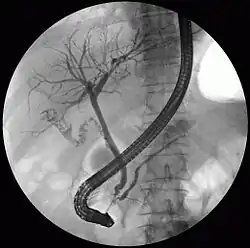

Fluoroscopic image taken during endoscopic retrograde cholangiopancreatography (ERCP). Multiple gallstones are present in the gallbladder and cystic duct. The common bile duct and pancreatic duct appear to be unobstructed.

The diagnosis of choledocholithiasis is suggested when the liver function blood test shows an elevation in bilirubin and serum transaminases. Other indicators include raised indicators of ampulla of vater (pancreatic duct obstruction) such as lipases and amylases. In prolonged cases the international normalized ratio (INR) may change due to a decrease in vitamin K absorption. (It is the decreased bile flow which reduces fat breakdown and therefore absorption of fat soluble vitamins). The diagnosis is confirmed with either a magnetic resonance cholangiopancreatography (MRCP), an endoscopic retrograde cholangiopancreatography (ERCP), or an intraoperative cholangiogram. If the patient must have the gallbladder removed for gallstones, the surgeon may choose to proceed with the surgery, and obtain a cholangiogram during the surgery. If the cholangiogram shows a stone in the bile duct, the surgeon may attempt to treat the problem by flushing the stone into the intestine or retrieve the stone back through the cystic duct.

On a different pathway, the physician may choose to proceed with ERCP before surgery. The benefit of ERCP is that it can be utilized not just to diagnose, but also to treat the problem. During ERCP the endoscopist may surgically widen the opening into the bile duct and remove the stone through that opening. ERCP, however, is an invasive procedure and has its own potential complications. Thus, if the suspicion is low, the physician may choose to confirm the diagnosis with MRCP, a non-invasive imaging technique, before proceeding with ERCP or surgery.